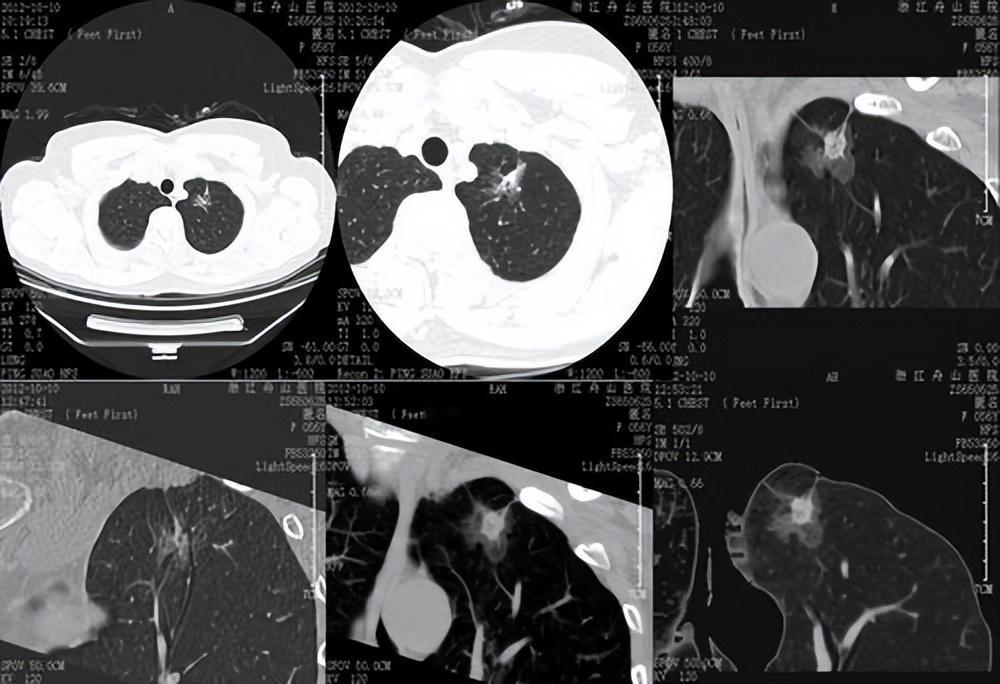

肺结节的 “善恶变形记”:一开始就坏,还是半路变心? 拿到肺结节报告时,很多人会疑惑:这小东西是天生恶性,还是后来 “变坏” 的?作为呼吸科医生,今天用通俗的话拆解答案。 其实两种情况都存在!部分结节从 “出生” 就是 “坏种子”—— 比如早期肺癌的原位癌结节,细胞一开始就带着恶性基因,只是初期长得慢、没症状,像潜伏的 “特务”。但更多结节是 “半路变心” 的:原本是良性的炎症、增生或良性肿瘤,长期在吸烟、空气污染、病毒感染等 “坏环境” 刺激下,细胞逐渐发生基因突变,慢慢从 “好公民” 变成 “癌细胞”。 关键区别在于结节的 “长相”:边界模糊、有分叶毛刺、密度不均匀的磨玻璃结节,可能是 “正在变坏” 或 “天生就坏” 的信号;而边界光滑、密度均匀的实性结节,多是良性 “老实人”。 但别恐慌!多数肺结节是良性的,即便有恶变风险,从 “良性” 到 “恶性” 可能需要几年甚至十几年。定期 CT 随访、及时干预,就能抓住 “变心” 的关键期,把风险扼杀在摇篮里。